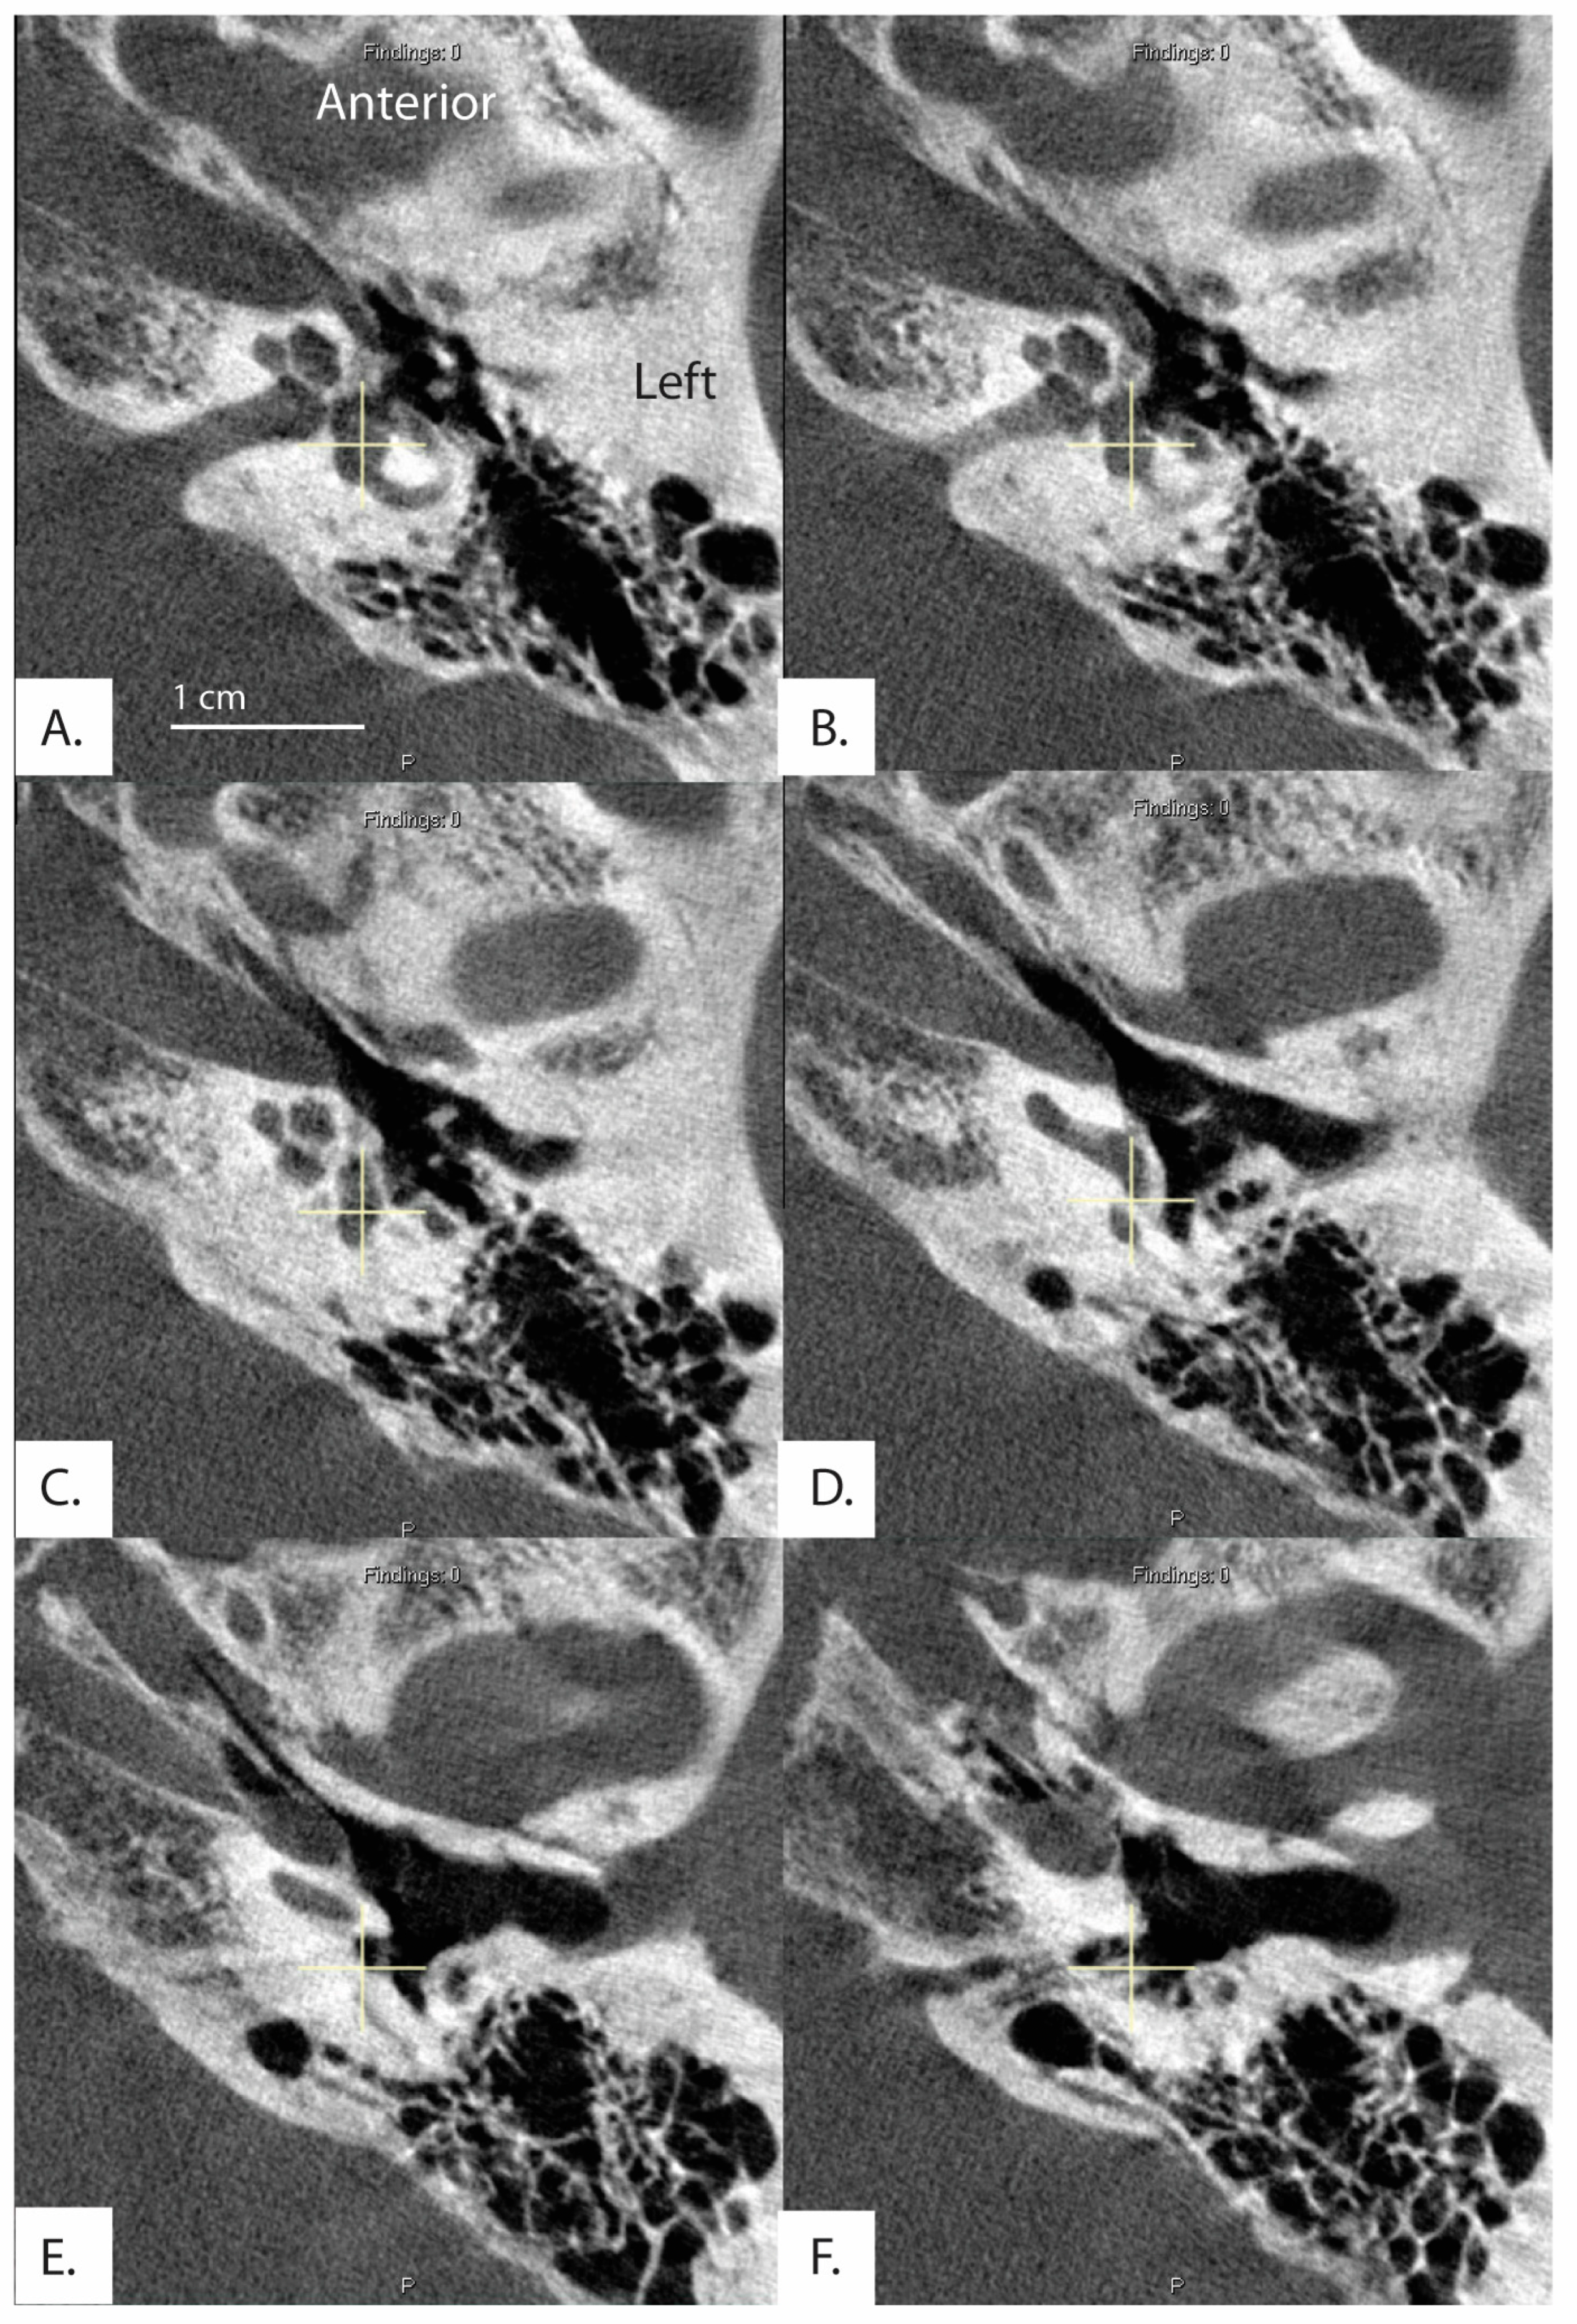

All measurements of the vestibular aqueduct were made in the plane aligned with the horizontal semicircular canal. Software developed by Bächinger et al. for measurements of the angle of the vestibular aqueduct was used [1]. As described in Bächinger et al., a predefined shape (magenta shape, Figure 1) was manually fitted to the vestibule and horizontal semicircular canal. As it is difficult to visualize the entrance of the vestibular aqueduct to the vestibule in most CT scans and therefore measure the proximal angle of the vestibular aqueduct, Bächinger et al. predetermined Line L1 (red line, Figure 1) based on histologic measurements and fixed it to the magenta shape at 14 degrees from the medial wall of the vestibule. Line L2 (green line, Figure 1) was manually adjusted to run parallel to the distal vestibular aqueduct near the operculum. The angle measured is the angle between L1 and L2 (Figure 1). Angles were assessed by author DJ and the first ten measurements were reviewed with the senior author BW. Measured angles were compared to the angles reported as thresholds in the Bächinger et al. publication [10]. The medical records for all patients were reviewed for a clinical diagnosis. Diagnosis of Meniere’s Disease was determined using the consensus criteria for the diagnosis of definite Meniere’s Disease as set by the Barany Society’s ICVD [17]. The diagnosis is based on 3 clinical symptoms: episodic vertigo, fluctuating aural symptoms (hearing, tinnitus, aural fullness), and low frequency sensorineural hearing loss [17].

Figure 1.

Example of temporal bone reconstruction from flat-panel CT imaging data. Ear (4L) measured using the tool developed by Bächinger et al. [1]. The magenta predefined shape is fitted to the vestibule and horizontal semicircular canal by altering the dimensions of the dashed rectangle. A red line is predefined by Bächinger et al. and fixed to magenta shape [1]. The green line is manually aligned parallel to the trajectory of the distal vestibular aqueduct. The inset shows a magnified view of the components used in the calculation of the angle, which in this case is 114.17 degrees and falls within the normal range.

In this study 462 (80.8%) ears had angles less than 120 degrees, 96 (16.8%) ears had angles 120 < > 140 degrees, and 14 (2.4%) ears had angles greater than 140 degrees (Table 2). All measurements for ears with angles > 140 degrees are shown in Figure 2. There were no differences among the groups in the ATVA (Figure 3). There were 13 adult patients (4.3%) with > 140 degrees. One patient had ears with > 140 degrees bilaterally. One patient with > 140 degrees had a clinical diagnosis of Meniere’s disease but not in the ear with > 140. The medical records of all individuals meeting the criteria for hypoplastic vestibular aqueduct (>140 degrees) were additionally reviewed. None of the 13 patients had a clinical diagnosis of Meniere’s Disease in the affected ear. These patients were diagnosed with a variety of otologic problems. Of the 14 ears, diagnoses included superior canal dehiscence syndrome (n = 3), thin bone over the superior semicircular canal (n = 1), intracochlear schwannoma (n = 1), otosclerosis (n = 1), or asymptomatic/presbycusis without associated symptoms of Meniere’s disease (n = 7). Images were reformatted in the planes of both the superior SCC and the posterior SCC and orthogonal to these planes. For the affected ears, imaging was interpreted by the radiologist as normal (n = 8), to have a dehiscent superior SCC (n = 3) to have thin bone overlying the superior (n = 1) or posterior (n = 2) semicircular canals. Other incidental findings include a prior transverse sinus stent (n = 1), bony exostoses of the external auditory canal (n = 1), and a prior right mastoidectomy performed for superior canal plugging (n = 1). None of the patients had a dehiscence of the posterior SCC. One ear had episodic aural fullness and two episodes of spinning vertigo, but with a high frequency hearing loss on pure tone audiometry, meeting the diagnosis of probable Meniere’s disease.

Figure 2.

Images and measurements for all ears with ATVA > 140 degrees are shown. Bächinger et al. software used to measure the ATVA [1]. Some ears use two images to calculate the angle. If the vestibular aqueduct and the vestibule are not visible in a single plane, the software provides an option to use both an image at the level of the vestibule and another image at the level of the distal VA to measure .